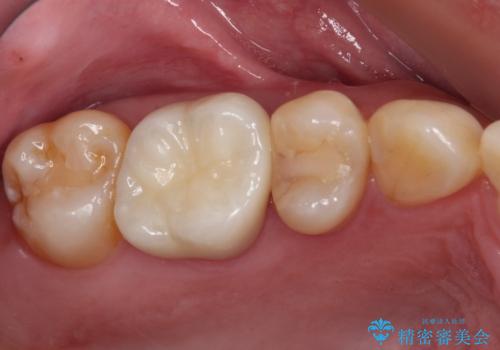

奥歯で噛みたい インプラントによる欠損補綴治療

- 抜歯をしたものの、インプラントにするか入れ歯にするか悩んでいるうちに2年以上経過してしまったとのことで来院された患者様です。

自分の歯のように噛めるようにしたいとのことで、インプラントによる欠損補綴治療を行うこととしました。

インプラントにはストローマン社のSLActiveを使用し、埋入から補綴までおよそ3か月と、短期間で治療を進めることができました。